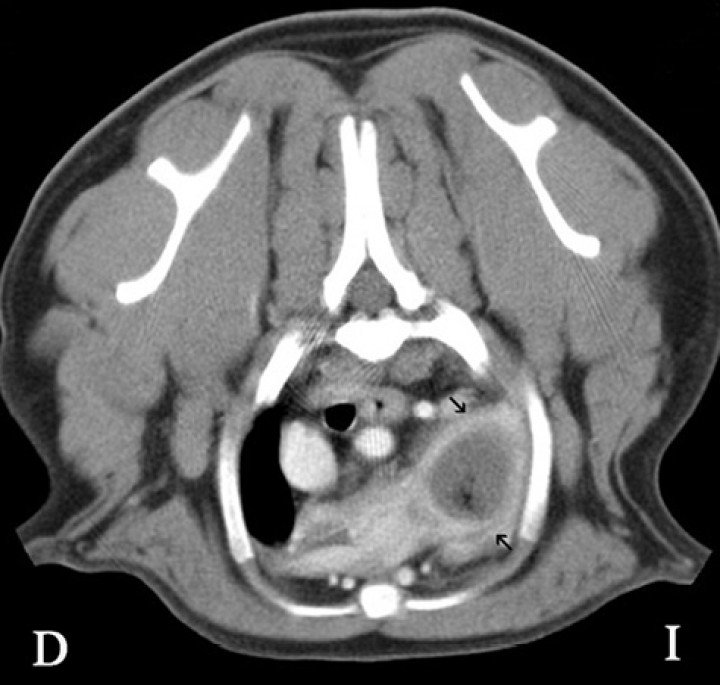

Figura 4

Imagen de tomografía computarizada (TC) del tórax en plano transversal en ventana de tejido blando tras la administración del contraste. Se visualiza en la zona del lóbulo craneal izquierdo un realce en anillo (flechas negras) con una zona central sin realce.

En el caso clínico que se presenta, la TC de la cavidad torácica evidenció una interrupción abrupta del bronquio lobar craneal izquierdo, observándose el lóbulo pulmonar craneal izquierdo (porción craneal y caudal) completamente consolidado con una pequeña zona enfisematosa en su porción más craneal, estando aumentado de tamaño y ocasionando una leve desviación hacia la derecha del mediastino craneal (Fig. 3). Tras la administración de contraste, el lóbulo presentó un realce en anillo con una zona central que no se realzaba con el contraste, siendo compatible con un área de necrosis o la formación de un absceso (Fig. 4).